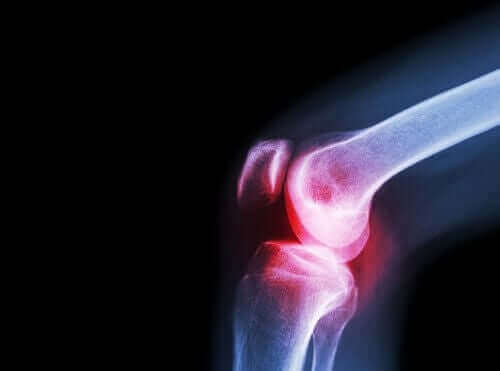

التهاب المفاصل الروماتويدي

هو مرض مناعي ذاتي التهابي مزمن يصيب عدد من المفاصل ويؤدي إلى أعراض عامة غير محددة.

إذا لم يتم التعامل مع هذه الحالة بشكل صحيح، يمكن أن تؤدي إلى تقييد الحركة بشكل كبير، وهو ما يؤدي إلى تخفيض جودة حياة المريض بشكل كبير.

فيما يتعلق بالأعراض، تؤدي الحالة إلى ظهور ألم وتصلب، وصعوبة في تحريك المفاصل الكبيرة والصغيرة في مناطق مختلفة من الجسم.

ولكن، أكثر الأعراض شيوعًا هو بلا شك التصلب الصباح، والذي يظهر في اليدين والقدمين على وجه الخصوص.

محفزات التهاب المفاصل الروماتويدي لا تزال غير معروفة. ولكن، كما ذكرنا، هو اضطراب مناعي ذاتي، ويوجد عوامل جينية وغير جينية تساهم في ظهوره.